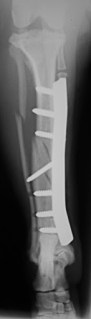

Ακτινογραφία κνήμης σκύλου αμέσως μετά την οστεοσύνθεση με μεταλλική πλάκα  και κοχλίες

Ακτινογραφία αμέσως μετά την

οστεοσύνθεση με μεταλλική πλάκα

και κοχλίες.